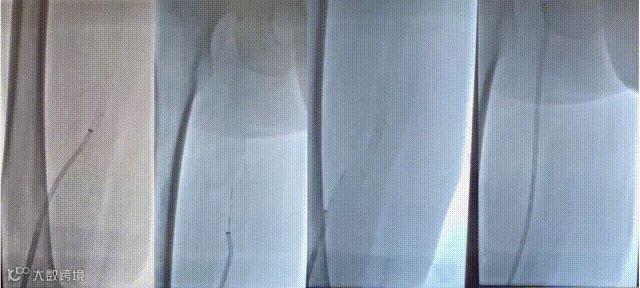

导入10F天航外周血栓抽吸导管+天戟分离器于大腔导管行机械血栓清除

导入(10*60mm)球囊行髂静脉扩张

(三)导入大腔吸栓导管,经腘静脉吸栓至股总静脉,吸出大量血栓,造影后栓塞血管开通。

(四)导入球囊(10*80mm)扩张髂股静脉,再次造影见髂总静脉闭塞